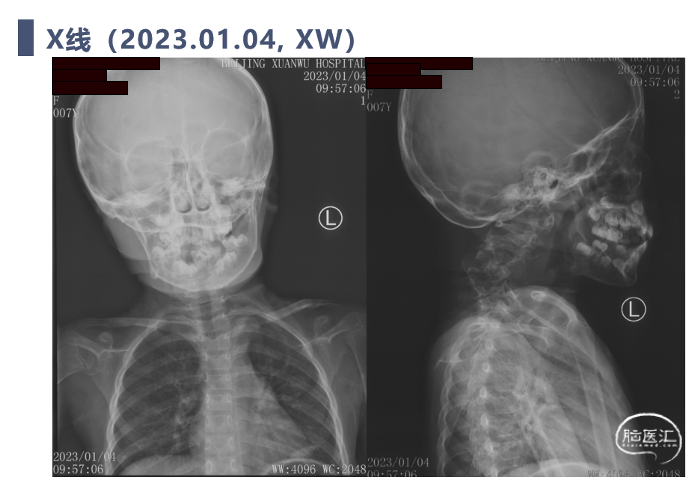

术前影像学检查

X线